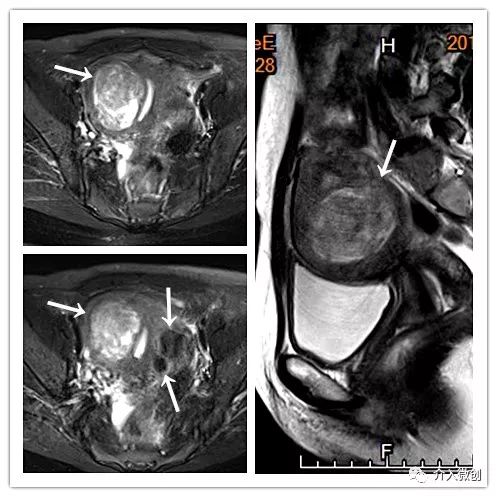

- MRI确诊为子宫多发肌瘤,行子宫动脉栓塞治疗。

MRI显示子宫多发肌瘤